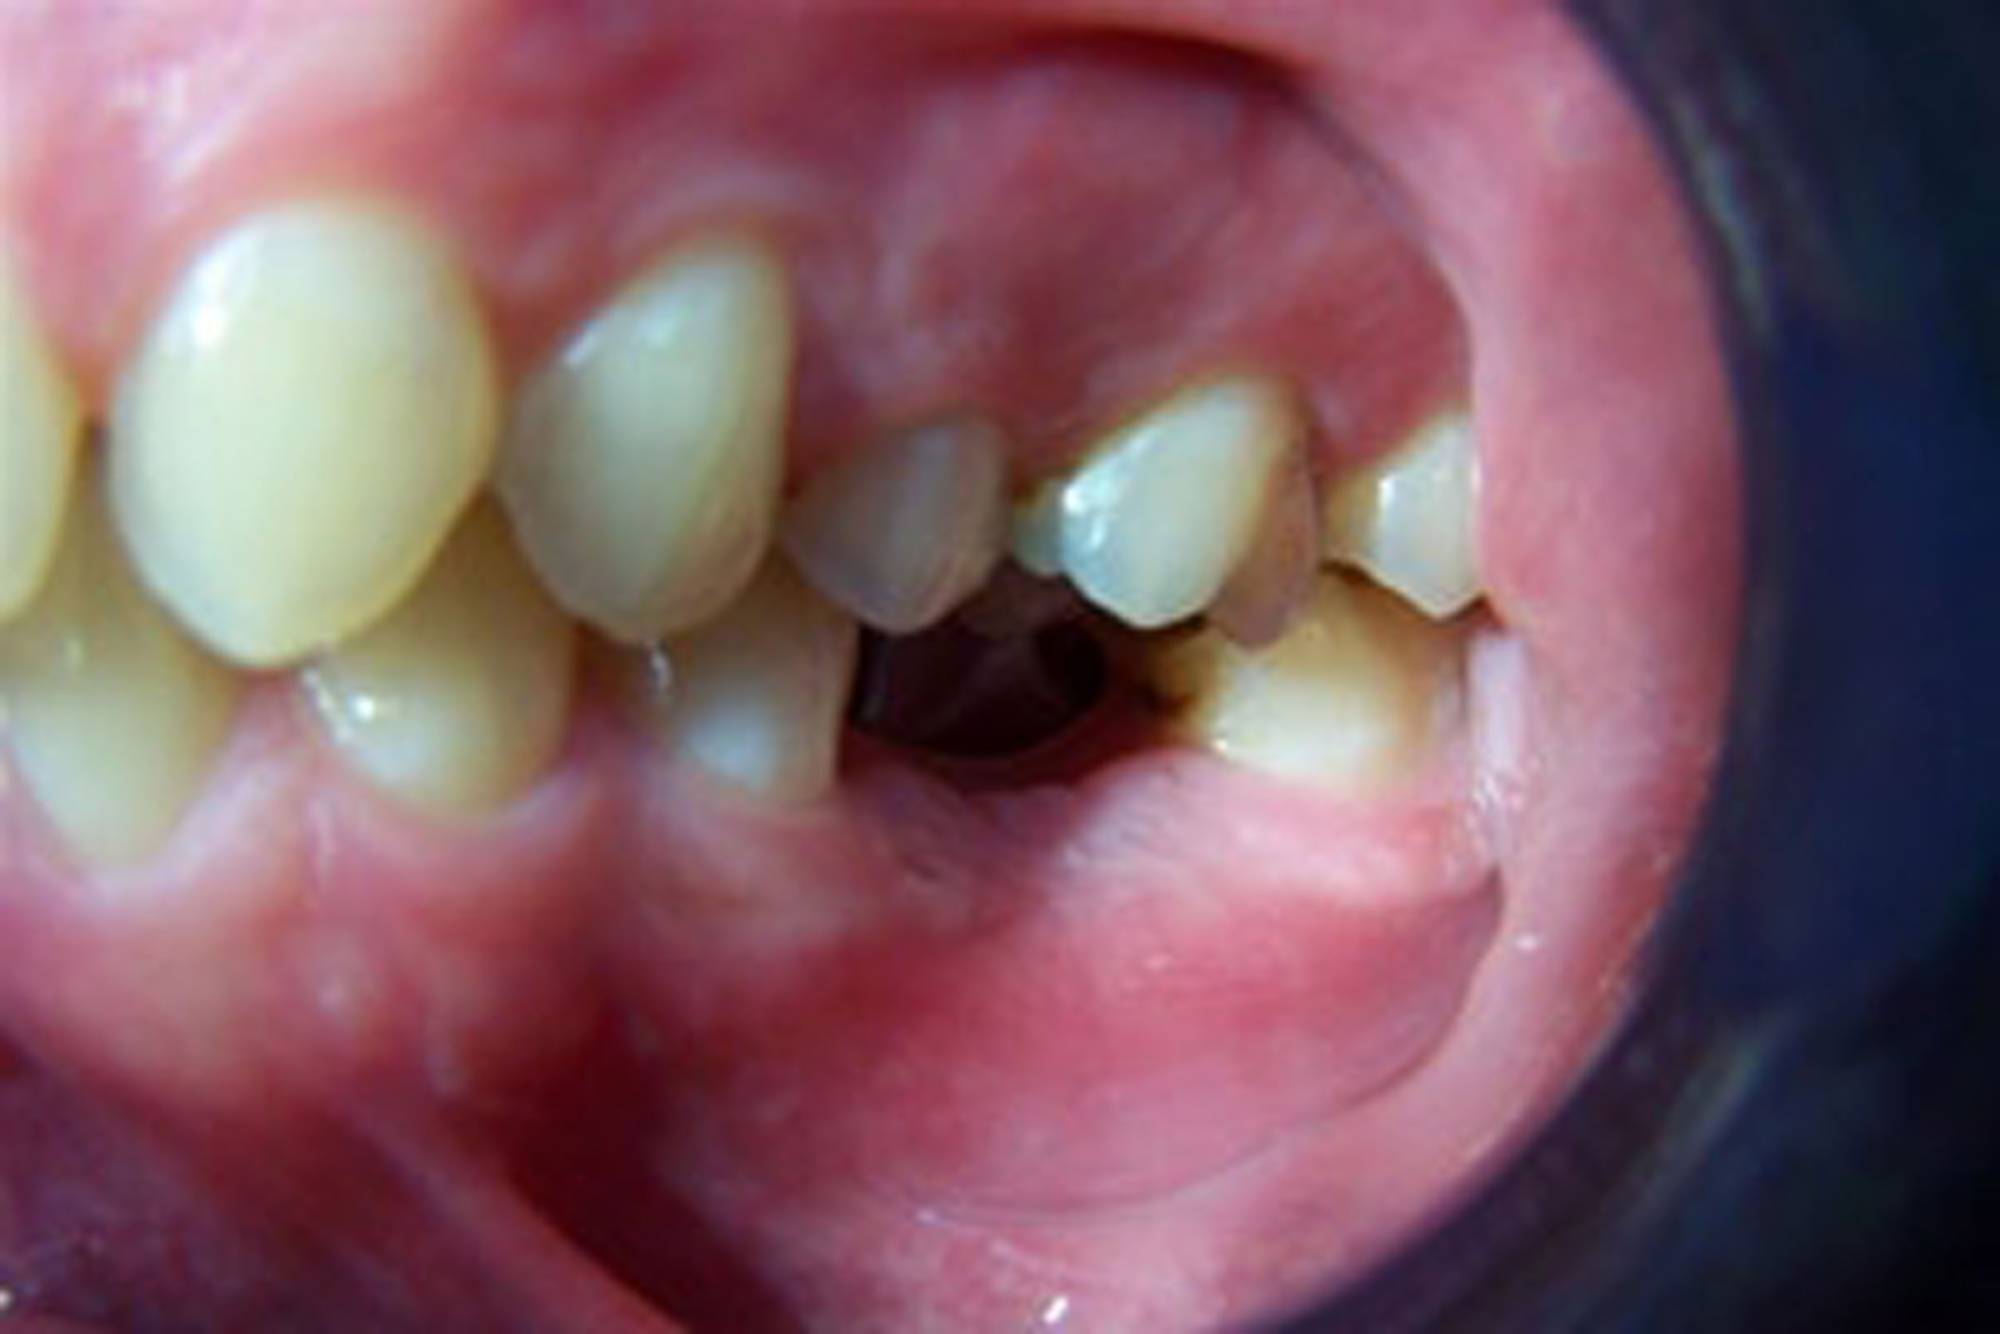

Quasi tutti possono ricorrere agli impianti, poiché sono una soluzione che presenta solo poche controindicazioni di carattere generale. Anche nei casi in cui non vi sia una sufficiente quantità d’osso per inserire l’impianto, è possibile ricorrere a tecniche di rigenerazione ossea guidata utilizzando biomateriali specifici e porzioni d'osso prelevate dal paziente stesso, per ricostruire la parte ossea mancante.